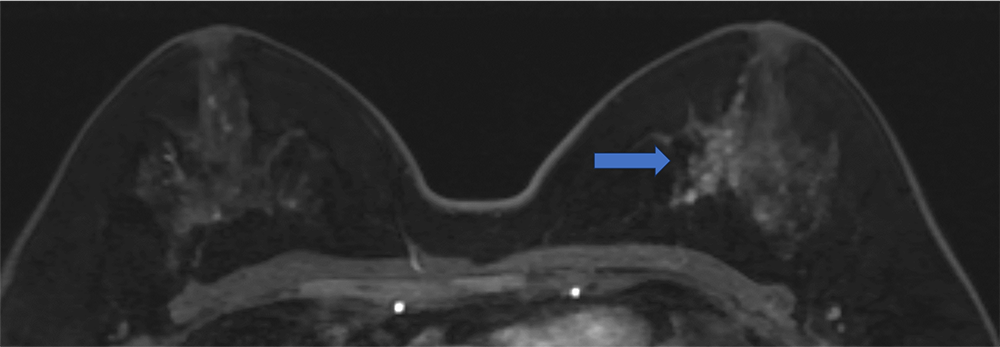

5. Ultrafast DCE 造影剤投与約20秒後、23秒後、26秒後

BPEが目立たないため、左乳房内側の病変が容易に同定できる

ultrafast MRI 造影剤投与

約23秒後